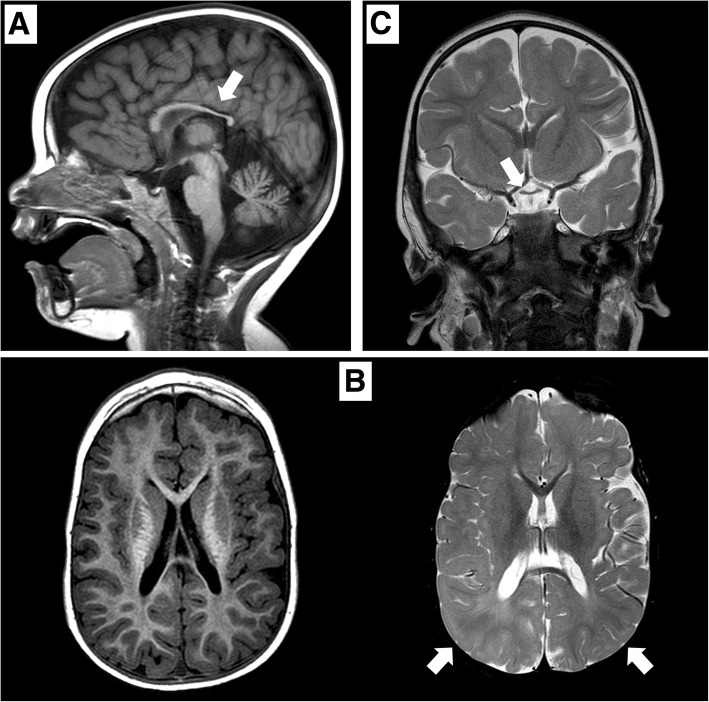

矢状位 T1 加权图像显示胼胝体发育不全(白色箭头)。 b 轴向 T1 加权(左)和轴向 T2 加权(右)图像显示胼胝体发育不全和双侧皮层下顶叶白质(白色箭头)中改变的、不明确的信号。 c 显示视交叉发育不全的冠状 T2 加权图像(白色箭头)

根据《人的基因序列变化与人体疾病表征》,过去有部分机构和医务人员认为德莫塞尔综合征不是遗传性疾病,甚至有人认为该病不是由基因引起的,德莫塞尔综合征发生的内在基因原因被忽视。佳学基因通过基因解码找到并定位了导致这一疾病发生的原因,提出了德莫塞尔综合征的遗传风险,并建议通过基因检测明确和排除风险,让后代、二胎不再患有德莫塞尔综合征,实现德莫塞尔综合征遗传阻断的目的。佳学基因病案集中一个患者是一名 2015 年出生的男孩,是健康父母的第二个孩子。 他有一个健康的姐姐,姐姐于 2011 年出生。他出生时妊娠 376/7 周,顺产(体重,2.4kg;z-分数,->1,65;长度,45-cm;z-分数, − 2.45;头围,31 cm;z 分数,- 1.84;Apgar 评分,1 分钟 8 分和 5〉 分钟 8 分)。 出生后 5 小时,他因低血糖(床旁检查,29mg/dl)被送入新生儿病房,并接受了 72 小时的静脉葡萄糖输注。 先天性巨细胞病毒感染的脑超声和实验室检查结果均正常。6个月大时的初步评估显示整体发育迟缓。 患者的体格、营养和身高对于他的年龄而言是正常的(z 评分,+ 0.64)。 检查显示小头畸形(z 评分,− 1.56)、畸形特征(薄上唇、尖腭、低植发、长人中、广泛的睑裂)、肢体异常(右脚趾和双脚足底垫植入异常) )、小阴茎和隐睾。患者出现全身性肌张力减退; 他无法实现头部控制,并表现出水平眼球震颤、眼球运动障碍和视力障碍。 没有癫痫发作史。 头颅磁共振成像 (MRI) 显示髓鞘形成延迟、胼胝体发育不全(图 1)和垂体发育不全。 没有闪光视觉诱发电位反应。